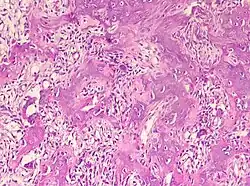

Sie bestehen aus einem stark gefäßversorgten „Kern“ (Nidus), der von einer rundlichen oder spindelförmigen Zone reaktiv wachsenden, verdichteten (sklerotischen) reifen Knochengewebes umgeben ist. Vorzugsweise sind Osteoid-Osteome in Ober- und Unterschenkelknochen lokalisiert. Überschreitet der Nidus eine Größe von 1,5 cm, wird die Veränderung als Osteoblastom bezeichnet.